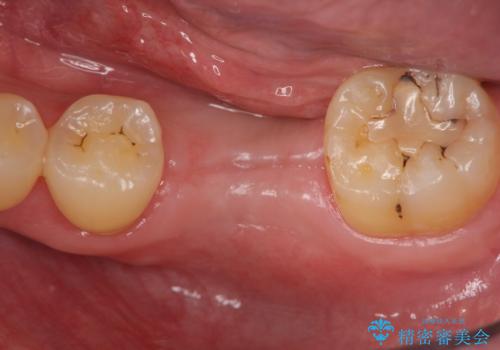

インプラントによる咬合機能回復

前後の歯は虫歯も治療歴もないため、前後の歯を削らなくてはいけないブリッジではなくインプラント治療による咬合機能回復を計画します。

- 46.2万円(仮歯・ストローマンインプラント・チタンカスタムアバットメント・ジルコニアクラウン)費用は治療当時の料金となります